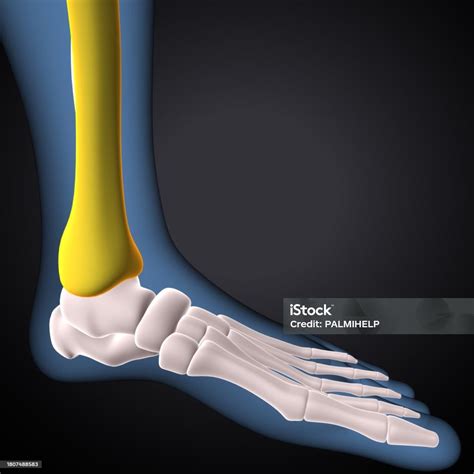

human anatomy male tibia shin bone stock illustration 520×620

human anatomy male tibia shin bone stock illustration

human anatomy male image photo  trial bigstock 390×470

human anatomy male image photo trial bigstock